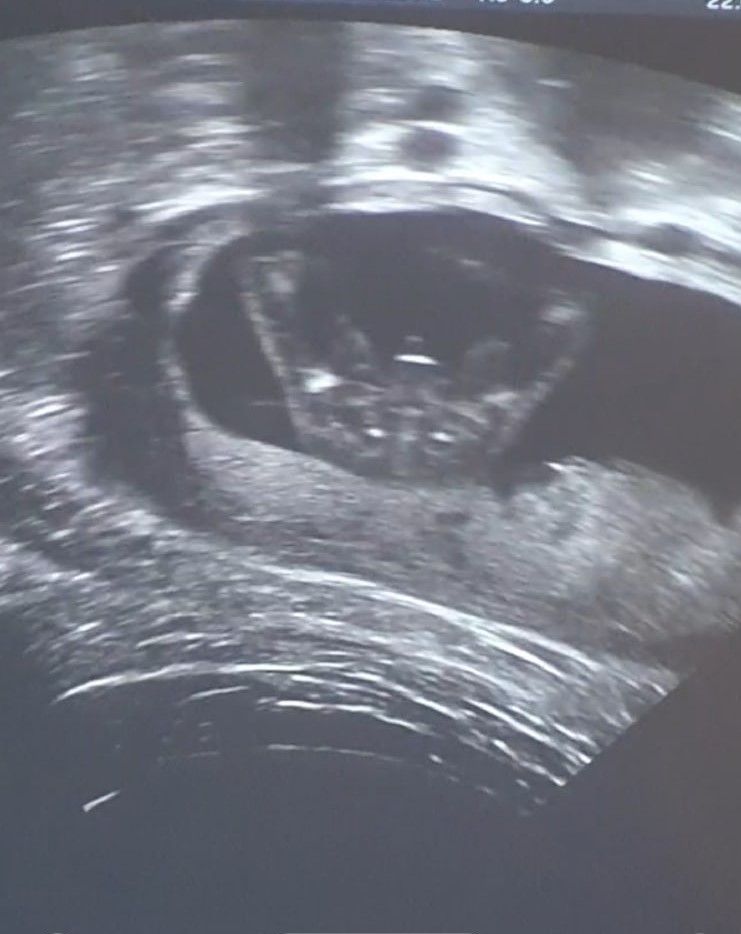

Сегодня ездила на цервикометрию чтобы проконтролировать шейку и решить отменять ли ночной утрожестан. В итоге шейка отличная, все закрыто и никаких признаков, что она захочет чудить нет. У меня как раз вчера последняя свечка была и утрик кончился, поэтому новый уже не покупала и перестаю его вставлять.

Показали на минутку малыша и между ножек. Какой же он классный! Врач посмеялась, сказала: "Сомнений нет, мальчик!" ))))